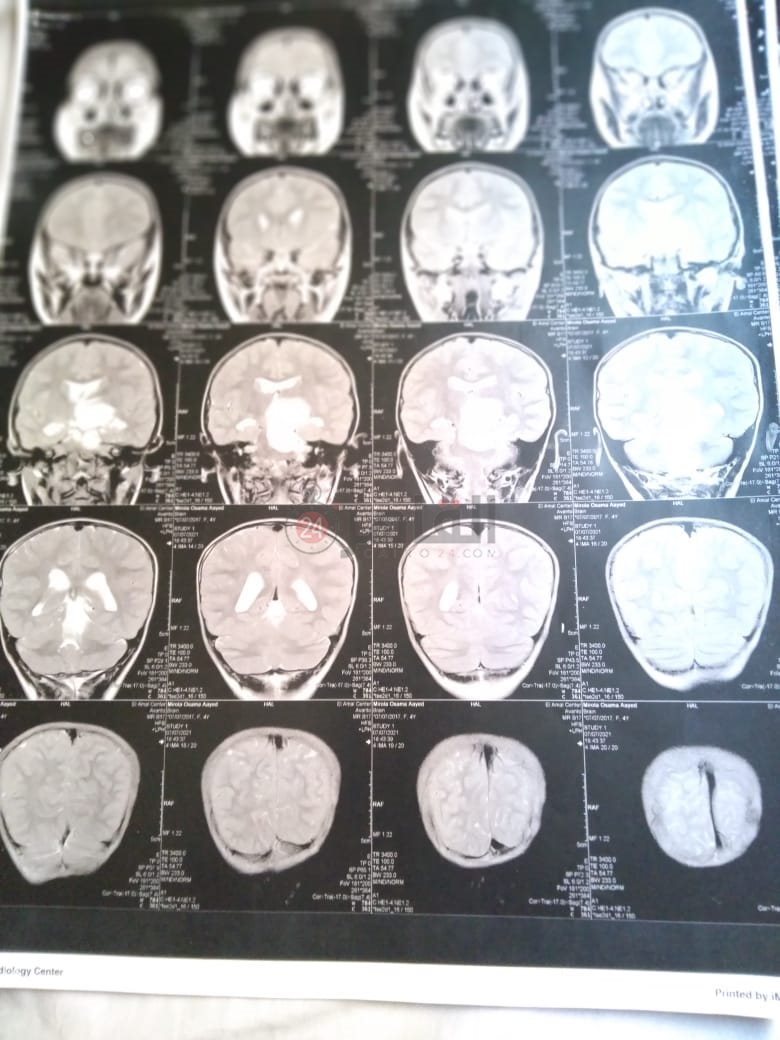

وأضاف: "أجرينا أشعة مقطعية لها لم يظهر بها أي شيء، ثم طلب الطبيب إجراء أشعة رنين على المخ، وهنا تبين وجود بؤرة سرطانية بالمخ، مشيرًا إلى أن:" الدكتور طلب مني أذهب إليه لوحدي من غير الأم والبنت، وقالي إن في ورم بس مش عارفين نوعه خبيث ولا حميد".

وأوضح أن حالة نجلته تتدهور بسرعة كبيرة، حيث أصُيبت حاليًا بشلل نصفي بالجانب الأيمن، لأن البؤرة حجمها 2.5 سم في 4.5 سم، ومرتكزة على جانبها الأيمن، مشددًا على أنها الحالة الأولى في العائلة التي تصاب بهذا المرض.